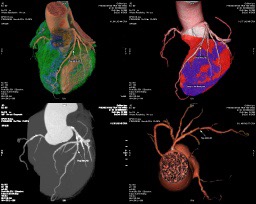

Bệnh nhân nam 66 tuổi, quốc tịch Nga đến Phòng khám Trái Tim Vàng vì tăng huyết áp mới xuất hiện. Kết quả MSCT động mạch vành cho thấy hẹp nặng 3 nhánh động mạch vành, vùng thiếu máu cơ tim diện rộng – dấu hiệu của bệnh mạch vành tiến triển.

Chẩn đoán bệnh mạch vành

Bác sĩ sẽ đánh giá thông qua:

-

Điện tâm đồ (ECG) và siêu âm tim

-

Điện tâm đồ gắng sức

-

Chụp MSCT động mạch vành – giúp xác định vị trí và mức độ hẹp chính xác nhất

-

Xét nghiệm máu kiểm tra mỡ máu, đường huyết và chức năng tim